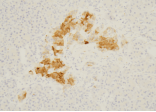

Synaptophysin

Synaptophysin(突触素)是分子量为38kDa的糖蛋白,主要存在于神经元突触前囊泡膜、肾上腺髓质、颈动脉体以及皮肤和内脏的神经性和上皮性神经内分泌细胞。此抗体主要用于标记神经内分泌细胞及其肿瘤,可用于鉴别肺小细胞癌和淋巴瘤,鉴别Merkel细胞癌与基底细胞癌,及作为嗜铬细胞瘤、节细胞神经瘤、福神经节瘤的诊断。